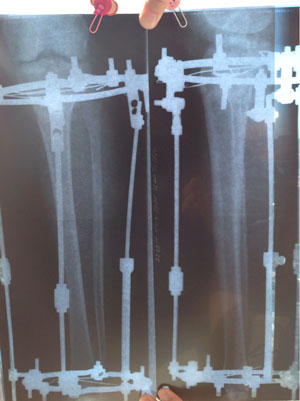

Рентген в 2 месяца.

Сращение идёт отлично, снятие аппаратов в 3 месяца!

Дата операции 04.02.2014г.

Дата снятия аппаратов 05.05.2014г.

Срок лечения 89 дней.